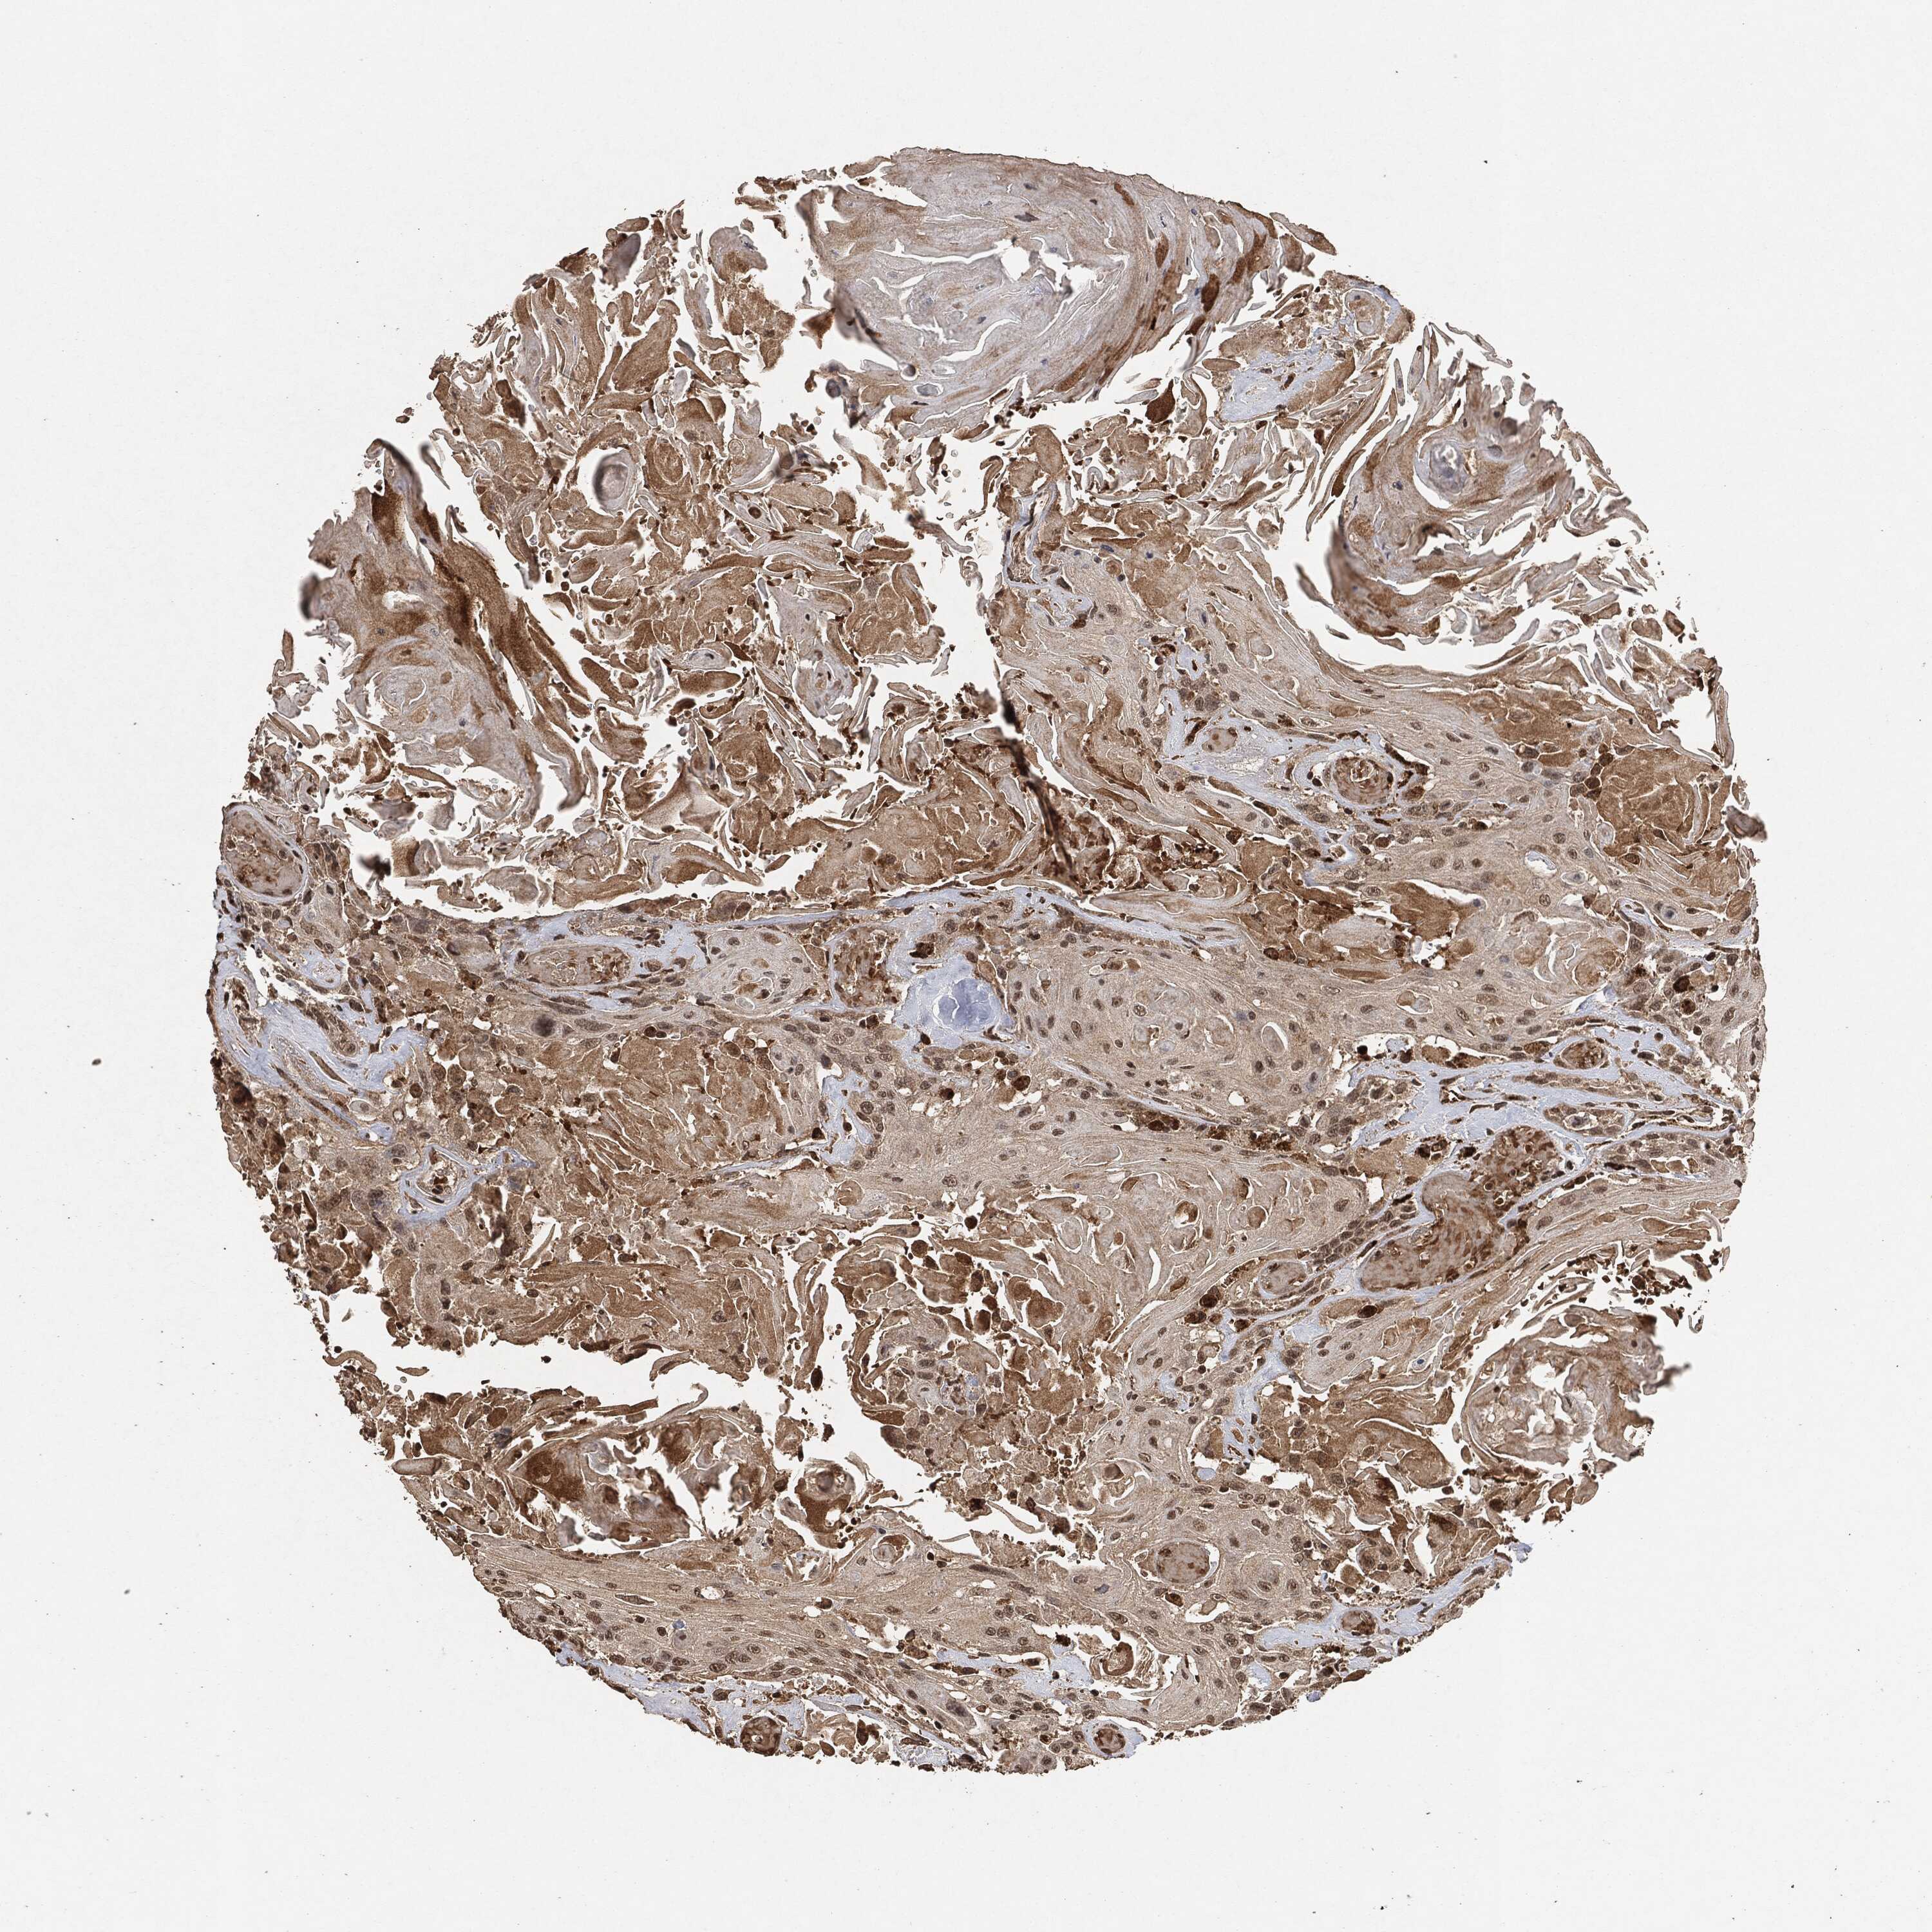

HEAD AND NECK CANCER - Protein expressioni

A mouse-over function shows sample information and annotation data. Click on an image to view it in a full screen mode. Samples can be filtered based on level of antibody staining by selecting one or several of the following categories: high, medium, low and not detected. The assay and annotation is described here.

Antibody stainingi

Antibody staining in the annotated cell types in the current human tissue is reported as not detected, low, medium, or high, based on conventional immunohistochemistry profiling in selected tissues. This score is based on the combination of the staining intensity and fraction of stained cells.

Each image is clickable and will lead to virtual microscopy that enables deeper exploration of all samples and also displays staining intensity scores, fraction scores and subcellular localization as well as patient and tissue information for each sample.